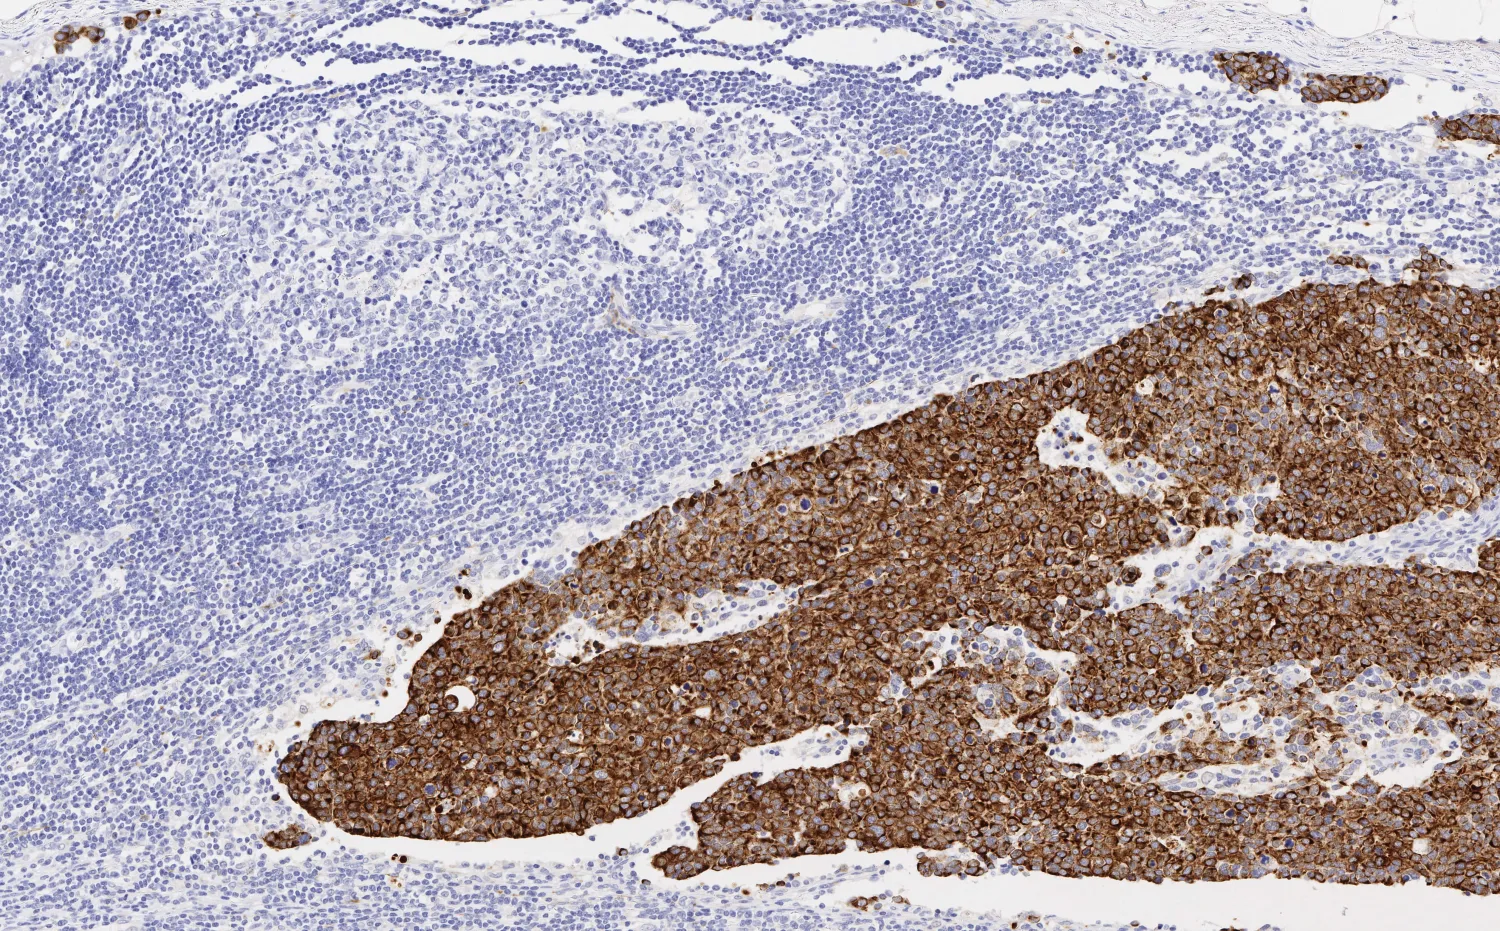

Metastatic breast cancer on a lymph node

Metastatic breast cancer on a lymph node, Leica Biosystems

To address this issue, Dr. Rimm and his lab developed a new, high sensitivity HER2 assay in 2022. “Our solution doesn’t force the pathologist to judge the level, but instead utilizes their ability to differentiate what's cancer and what's not.” With the new assay, the pathologist indicates the boundaries between tumor and healthy tissue, then HER2 antibody binding is measured with immunofluorescence and compared to a standard curve. In Dr. Rimm’s experience, this approach dramatically increases the accuracy, reproducibility, and sensitivity of the assay. “We're about 10 times more sensitive than the average HER2 test,” Dr. Rimm says.